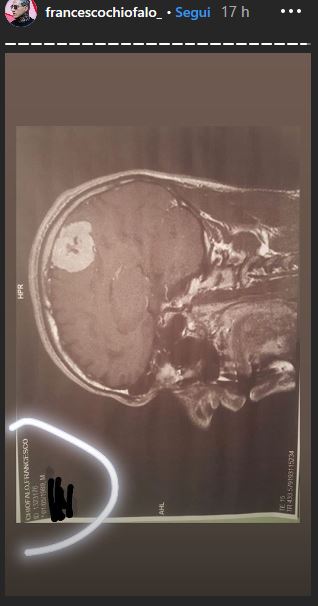

Chiofalo ha scelto di mostrare anche le immagini della massa tumorale che ha in testa, visibile anche a chi non è del mestiere, e ha ammesso che subito dopo le feste si dovrà sottoporre ad un delicato intervento che ha l’80% di non riuscita, con alte probabilità di invalidità permanente. L’ex fidanzato di Selvaggia Roma non ha scelta e si dovrà operare per forza: i medici sono stati molto chiari. Il ragazzo conclude dicendo che in questo periodo sarà assente dai social e che non sa se e quando potrà tornare a mostrarsi in video.